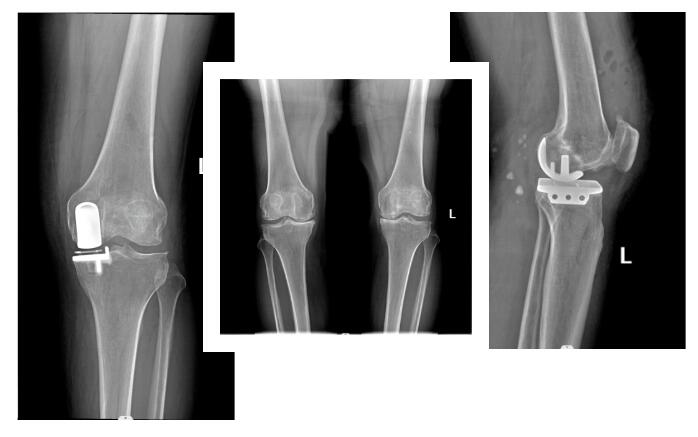

今年5月,骨科接診到一例96歲高齡髖部骨折患者。據(jù)了解,老人在家不小心滑倒,出現(xiàn)左髖部疼痛,左下肢短縮,因?yàn)榕陆o子女添麻煩就自行在家休息。隨后,因長期臥床,臀部出現(xiàn)大面積褥瘡,疼痛不已。輾轉(zhuǎn)多家醫(yī)院,均面臨手術(shù)風(fēng)險(xiǎn)大治療難度大,治療無果,最終在同小區(qū)鄰居建議下,子女慕名來到衡陽華程醫(yī)院骨科中心找到楊富才主任就診,通過影像檢查,結(jié)果顯示老人右側(cè)股骨頸骨折。在詳細(xì)查體了解老人身體情況后,楊富才主任建議老人開展“右側(cè)人工股骨頭置換術(shù)(Super CAP)”。

QQ截圖20221112152523.jpg

Super CAP較傳統(tǒng)人工股骨頭置換入路的優(yōu)點(diǎn):(1)切口小: 切口長度約6 cm(傳統(tǒng)后側(cè)入路為15cm),手術(shù)創(chuàng)傷較;(2)術(shù)中顯露更加清楚,術(shù)中出血較少,50ml,無需置管引流(傳統(tǒng)入路術(shù)中及術(shù)后出血700-1000ml);(3)術(shù)后恢復(fù)快,術(shù)后當(dāng)天麻醉6小時(shí)后即可下床活動(dòng),5-7天可出院,由于縮短了臥床和住院時(shí)間,因而降低了護(hù)理成本和患者的經(jīng)濟(jì)負(fù)擔(dān);(4)術(shù)后人工關(guān)節(jié)不易脫位(傳統(tǒng)入路極容易發(fā)生關(guān)節(jié)脫位)。

QQ截圖20221112152601.jpg

由于老人年事已高,還伴有糖尿病、高血壓、下肢深靜脈血栓等疾病,手術(shù)、麻醉風(fēng)險(xiǎn)極高。但如果不手術(shù),老人長期臥床后,容易加重褥瘡,引發(fā)多種并發(fā)癥,甚至威脅生命。

QQ截圖20221112152636.jpg

經(jīng)過反復(fù)考慮,患者家人還是決定配合醫(yī)生完成手術(shù)。楊富才主任帶領(lǐng)骨科團(tuán)隊(duì),在麻醉科、手術(shù)室、重癥醫(yī)學(xué)科、心內(nèi)科、呼吸內(nèi)分泌科等多學(xué)科團(tuán)隊(duì)的共同協(xié)作下,成功地為老人實(shí)施了右側(cè)人工股骨頭置換術(shù)(Super Cap)。手術(shù)第二天,老人使用助行器下床活動(dòng)行走,術(shù)后7天康復(fù)出院,2個(gè)月的回訪中我們得知,老人現(xiàn)在已經(jīng)能夠脫離助行器自由活動(dòng)了。